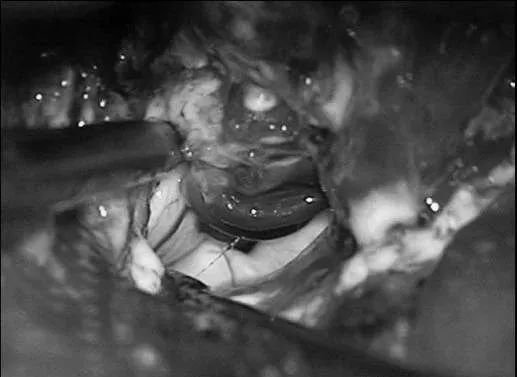

▼AChA经脉络裂进入颞角,在前方供应AVM,lPChA在后方供应AVM。

▼通过ITG经皮层显露可以充分显露颞角,达到全切AVM。

颞角AVM切除像颞底AVM一样通过颞部开颅(1步)、通过颞下回(ITG)经皮质入路。病人取仰卧位,头向侧方偏转90°,降低顶点以获得一朝向颞角的向上的角度。以耳上为基底的马蹄形切口、颞部开颅。入路在颞下回下部,角度对着脑室,保持在Meyer’s环内的视放射之下。Meyer’s环从上面越过颞角(2步)。导航有助于确定该入路。一旦进入颞角,沿其轴纵向打开,以完整看到AVM。直到切除结束才能够看到下ChorV和BVR(3步)。在脉络裂近端丛点之后辨认AChA,在脉络裂远端病变之后可见lPChA供血(4步)。先阻断AChA供血血管(5步),但是另外的自脉络丛的供血血管在内侧缘,从近端向远端继续分开脉络裂阻断这些脉络丛供血血管。需要向前用力,将一部分AVM移向外侧(6步)。优先通过脉络丛和穹窿伞(伞带)之间的脉络膜,从下方打开脉络裂,避开上面的尾状核尾部和丘脑下部。然后一步切除的是汇入BVR的引流静脉和残留的来自lPChA的供血血管(7步)。虽然没有严格意义上的语言功能,但是像其它脑室AVM一样,颞角AVM与丘脑、尾状核(尾部)、穹窿(伞)和海马相邻。